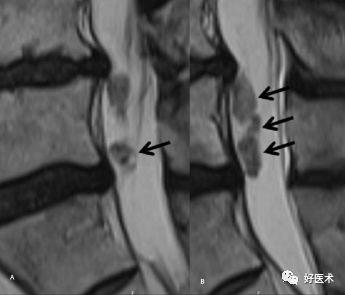

我们先来看一个病例:

图示:谭军教授团队提出的颈椎间盘突出的形态学分型示意图

诊断